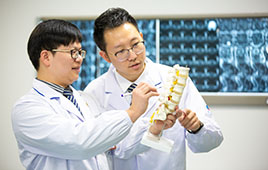

海鹽邦爾醫院是浙江邦爾集團旗下數十家連鎖醫院之一,是一家以骨科(創傷骨科、手足外科、脊柱外科、關節外科等)、內科(心血管內科、呼吸內科、消化內科(胃腸鏡)、腎內科(血透)、重癥醫學科(ICU)等)、非手術治療頸肩腰腿痛、泌尿外科、急診醫學科、婦科、全科醫療科、中醫科、口腔科、健康/職業健康體檢、康復理療科等的國家二級乙等綜合醫院。

醫院位于武原街道城東路1322號(縣交警大隊東800米),總建筑面積達14000余平方米,開放床位300余張;已開通核磁共振醫保結算。 特色設備: 1.5T超導型磁共振成像儀、16排螺旋CT、口腔CT、500MA程控X光機、移動式C型臂手術X光射線機、機器人“智微天眼”手術導引與反饋系統、奧林巴斯CV-290電子胃腸鏡、進口彩色B超、高清型椎間孔鏡、關節鏡、臭氧治療儀、全自動生化分析儀等。